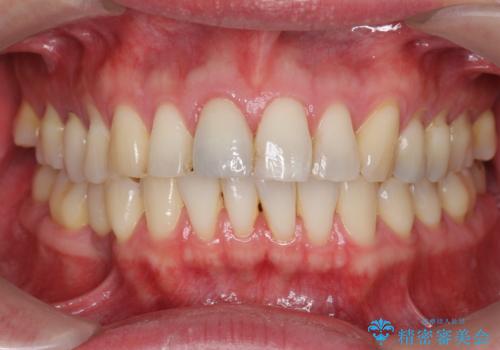

周囲の歯の色調に合わせた、自然なセラミック治療を行うことができましt。